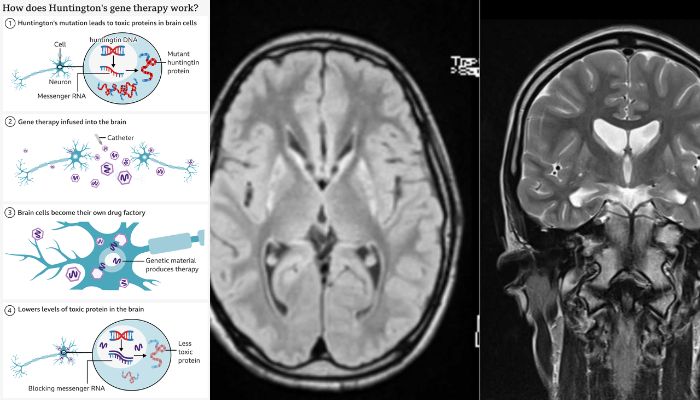

The new treatment consists of a gene therapy that is given to patients during 12 to 18 hours of sensitive brain surgery.

Huntington’s disease is caused by a mutation of a gene called the huntingtin gene, turning the normal protein into a killer of neurons.

The proposed gene therapy utilizes cutting-edge gene silencing technology and genetic medicine combining gene therapy.

The procedure starts with the altered virus that contains a specially designed sequence of DNA, which is infused into the brain using MRI.

The virus delivers the new piece of DNA inside brain cells and activates it. As a result, the DNA turns neurons into a factory, helping them to prevent their own death.

The cells also produce microRNA that helps in disabling instructions being sent from cells’ DNA for producing mutant huntingtin, thereby leading to reduced levels of mutant gene.